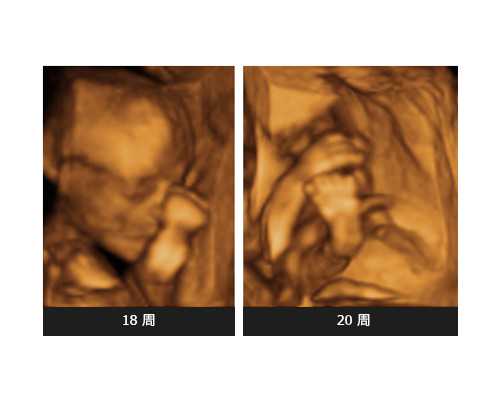

为什么那么多孕妇选择香港验血检测宝宝的性别?许多孕妈妈们通过各种各样的民间传统预测男女的办法进行预测判断男女,但没有任何一个办法可以使人信服。在怀孕四五个月以后,有的孕妈妈们会选择去医院做B超进行预测宝宝的性别,B超检查就是通过观察宝宝的生殖器官进行判断的,当孕妈妈到达这个时期以后,肚子里的宝宝已经有了一个基本雏形,不过还是存在很多的不利因素会影响结果的预测,胎儿姿势角度或者脐带的位置都会经常使最终的真实结果与预测结果大相径庭,翻盘的几率很大,而且在我们国家内地是不允许通过任何方式提早知道宝宝的性别的。